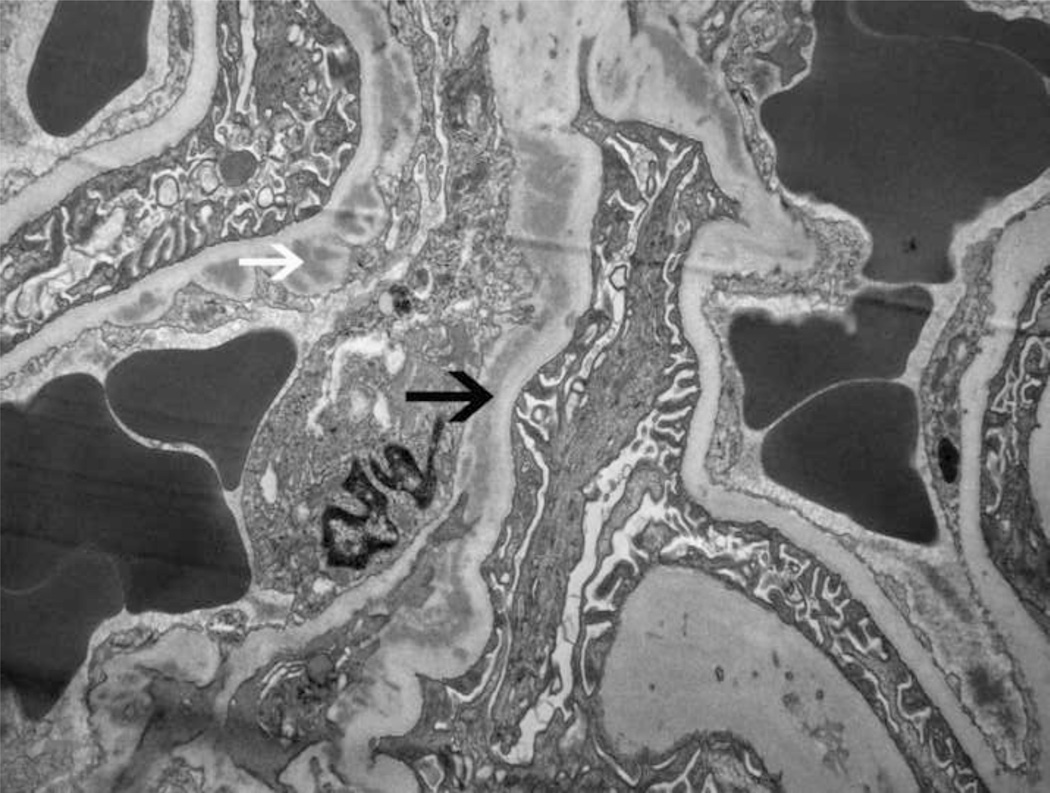

Twenty glomeruli were present for light microscopic evaluation, one of which was globally sclerosed. Two glomeruli showed segmental scars with adhesion of the scarred segments to the Bowman’s capsule. Nine of the remaining 17 glomeruli showed large circumferential cellular crescents (Figure 1A and B), with many areas of segmental fibrinoid necrosis (necrotizing lesions). Few intracapillary neutrophils were also noted, but most of the glomeruli not within the region of the crescents or necrosis appeared unremarkable and did not show any proliferative or exudative features. There was no interstitial inflammation present. Tubules contained RBCs and RBC casts. There was no significant tubular atrophy or interstitial fibrosis present. Vessels were unremarkable. Immunofluorescence studies revealed 7 glomeruli, one of which was globally sclerosed. The glomeruli showed bright granular 3+ mesangial and capillary wall staining for C3 (Figure 1C). In the glomeruli, IgG, IgA, IgM, C1q, kappa and lambda light chains were undetectable. Electron microscopy revealed mesangial and paramesangial electron dense deposits (Figure 1E). A few subepithelial “hump-like” deposits (Figure 1F) and a few small subendothelial and intramembranous deposits were also present (Figure 1G). Sausage-shaped large electron dense deposits were not present along the glomerular basement membranes. Based on these findings, the initial kidney biopsy diagnosis was of a post-infectious GN, with crescents and necrosis.

Figure 1. Kidney biopsy findings.

(A) Low power view of 4 glomeruli, 3 with crescents and 1 unremarkable (Jones stain 10×). (B) High power image of a glomerulus with a large circumferential crescent and necrotizing lesion. Note absence of endocapillary proliferation, or mesangial or membranoproliferative features (Jones stain, 40×). Immunofluorescence studies reveal (C) bright 3+ staining for C3 in the mesangium and along capillary walls (40×), and (D) bright fibrinogen staining in the glomerular tufts indicating fibrinoid necrosis (necrotizing lesion). Electron microscopy reveals (E) mesangial and paramesangial deposits with a fuzzy/waxy character (black arrows point to deposits) (5800×); (F) a subepithelial hump (7400×); and (G) few subendothelial (white arrow) and intramembranous deposits (black arrow)(7400×).

A review of the biopsy showed some features that were atypical for postinfectious GN, but instead were suggestive of a unique and severe crescentic and necrotizing GN resulting from an abnormality in the alternate pathway of complement (alternative pathway).(3) These included the following: 1) Many glomeruli did not show endocapillary proliferation or mesangial proliferation; 2) Immunofluorescence studies showed bright 3+ staining for C3 in the mesangium and along capillary walls and the absence of immunoglobulin staining; and 3) Many mesangial and paramesangial deposits, few subendothelial and subepithelial deposits, and few waxy intramembranous deposits were noted on electron microscopy. In our experience, the strong 3+ staining for C3, absence of immunoglobulin staining, intramembranous and occasional subepithelial deposits are good markers for GN resulting from dysregulation of the alternative pathway. Thus, the alternative pathway was evaluated and this led to rather surprising results.

Immunofluorescence microscopy revealed bright C3 staining in the mesangium and along capillary walls and complete absence of Ig staining. In addition, small waxy intramembranous, subendothelial, and subepithelial deposits suggested complement deposits (as opposed to Ig-containing deposits, which appear darker and more sharply demarcated). These findings prompted assessment of the alternative pathway, which to our surprise revealed a polymorphism in the sequence corresponding to SCR19 of CFH (Figure 2), an extremely unusual finding in the setting of crescentic and necrotizing GN since mutations in SCR19 have not been previously described to cause C3 GN or DDD. Evaluation also revealed 2 copies of the H402 allele of CFH, and in C3, 2 copies of the G102 allele and 1 copy of the L314 allele. These variants of CFH and C3 are causally associated with increased baseline alternative pathway activity even in healthy controls and are linked to both C3 GN and DDD.(9–11)